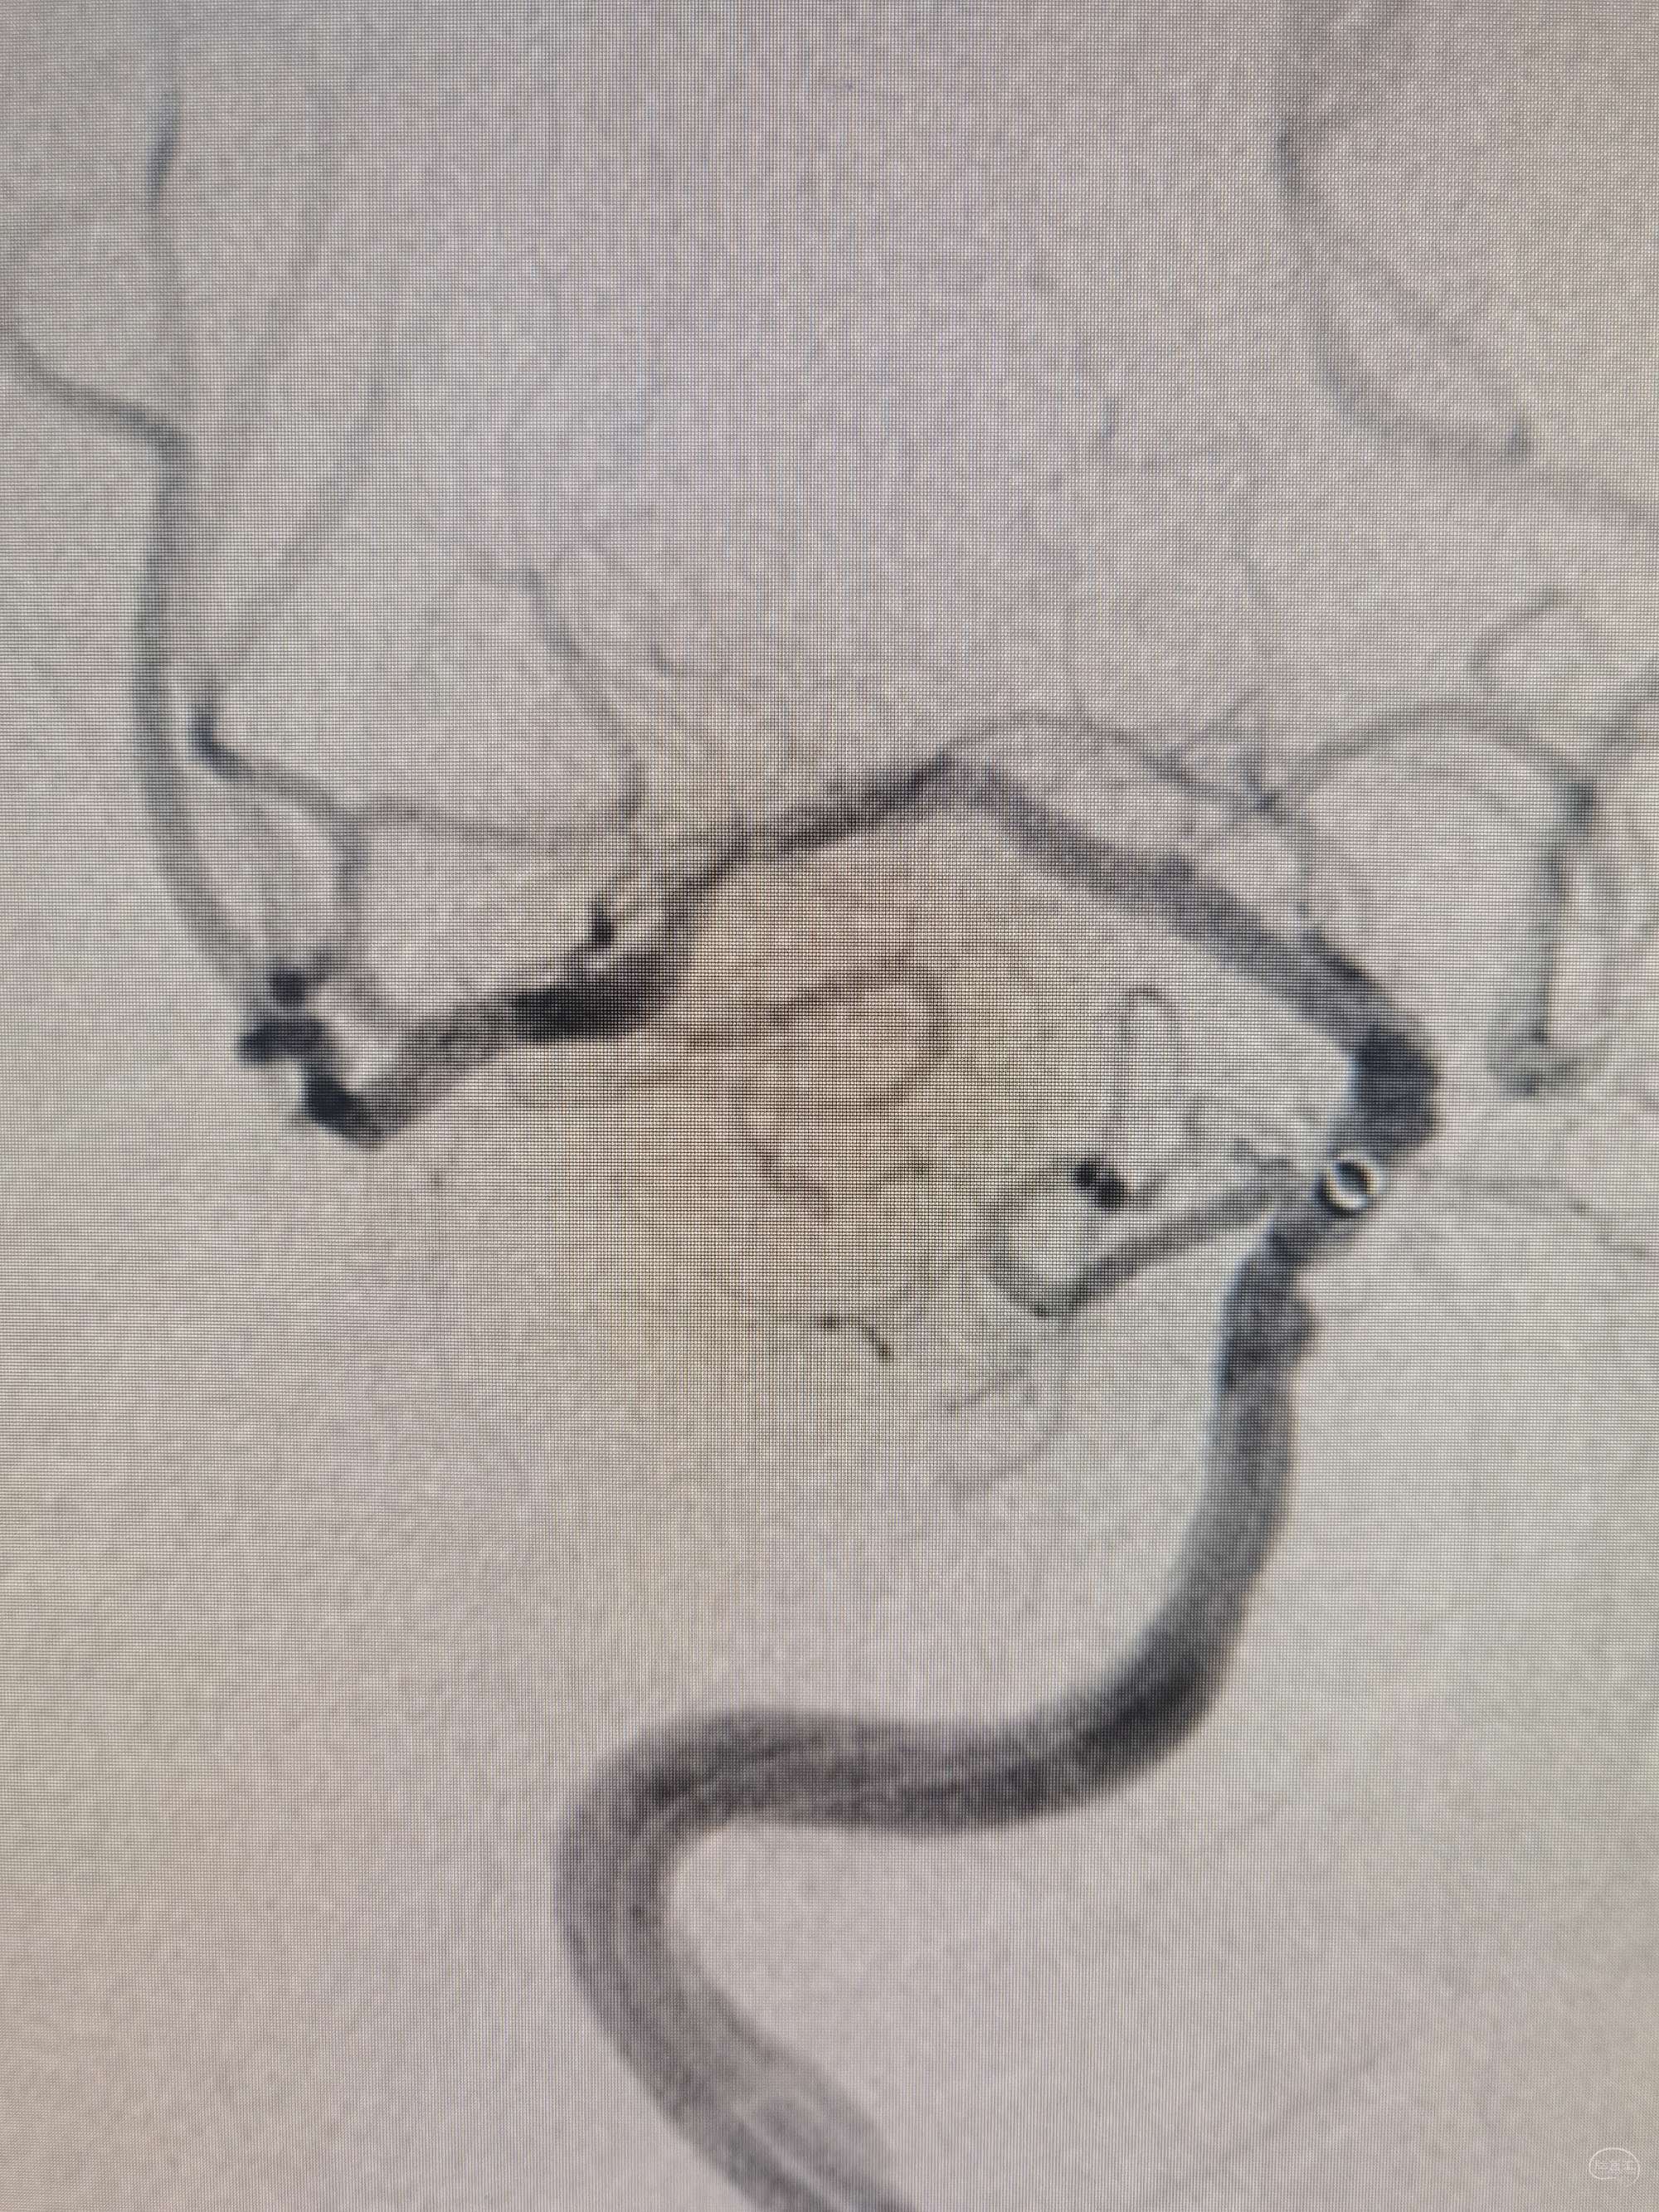

1.5*15颅内球囊命名压缓慢扩张,缓慢泄

扩张后观察5min血流及局部情况

不行,替罗非班5ml经中间导管缓推后,持续静脉泵入

替罗非班后再看: